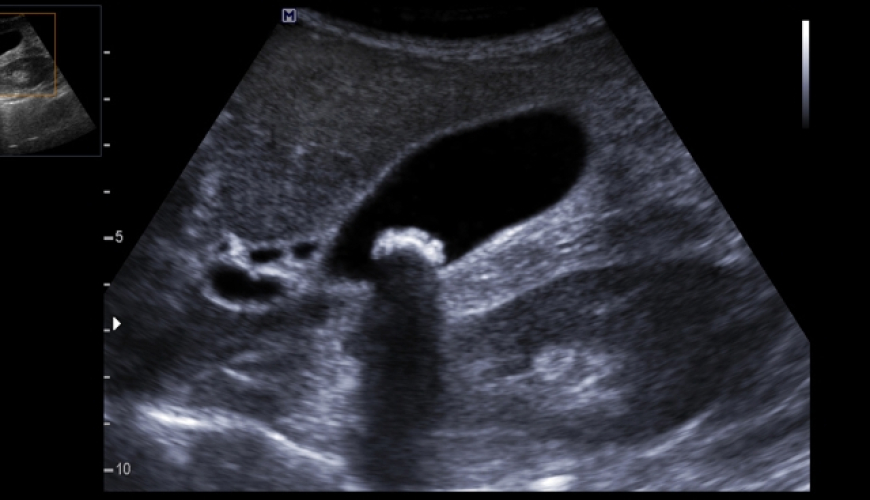

Ultrasəs müayinəsi

tibbdə aparılan əsas müayinə üsullarından biridir. Exolokasiya prinsiplərinə əsaslanan bu müayinə metodu orqanizmə zərər vurmadan daxili orqanlar və boşluqlar haqda dəqiq məlumat vermək imkanına malikdir.USM apparatı müvafiq datçik vasitəsilə orqana yönəldilmiş ultrasəs dalğalarının əks olunma tezliyini qeydə almaqla orqanın ölçüsü , forması , exogenliyi və s. barədə informasiya formalaşdıraraq ekranda göstərir.

Ultrasəs müayinısinin prinsipi sadədir: USM ötürücüsü səs dalğalarını xüsusi ucluqlar vasitəsilə toxunulan nahiyəyə ötürür. Orqanlar bu dalğaları əks etdirir və onlar yenidən ötürücüyə qayıdır və bu vasitə ilə monitorda müvafiq görüntü əks olunur. Qeyd olunan kimi USM-müayinə təhlükəsizdir, belə ki, insan heç bir şüalanmaya məruz qalmır. USM bir çox xəstəliklərin diaqnozlaşdırılması və ya orqanizmdə heç bir problem olmadığını təsdiqləmək üçün unikal vasitədir.